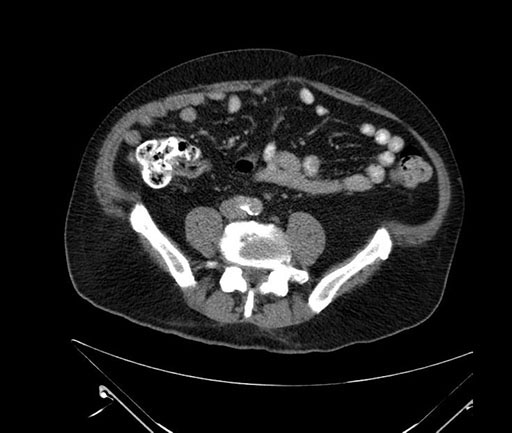

Coronal - stented